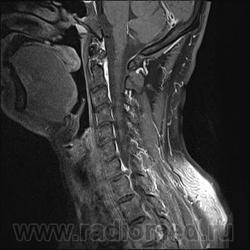

Грыжа диска. А где аксиалы?

Шейный остеохондроз.Грыжа С7-Th1.Не исключено наличие миелопатии на этом уровне, но боюсь ошибиться-изображения мелковаты ,идаже кажется, что есть повышение МРС от спинного мозга по Т1( скорее всего-артефакты?).

Левосторонняя парамедианная с компрессией корешка.

а это не перидурит??? смотрели месяц назад (в начале заболевания) было меньше.

Посмотрите на STIRе. Если жидкости нет, то простая грыжа. На этих сканах вообще-то жидкости не видно. За месяц грыжа могла и подрасти, смотря как лечили.

По-моему, только грыжа.

У меня такое мнение, хотя я не лучевик. Там из центра к правому краю рост бяки, возможно неври- или менинги- ома.